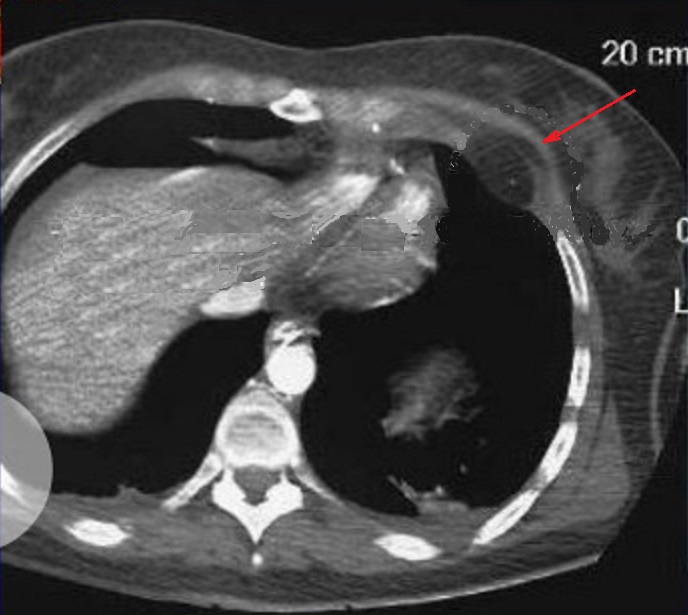

Espect metastatique de

tumefaction de la paroi thoracique droit et de

lyse de destruction osseuse correspondence du

côté droit d'une tumeur metastatique ( fleche rouge

) à origine de cancer pulmonaire ++ droit . Image

radiologique TDM en coupe axial |